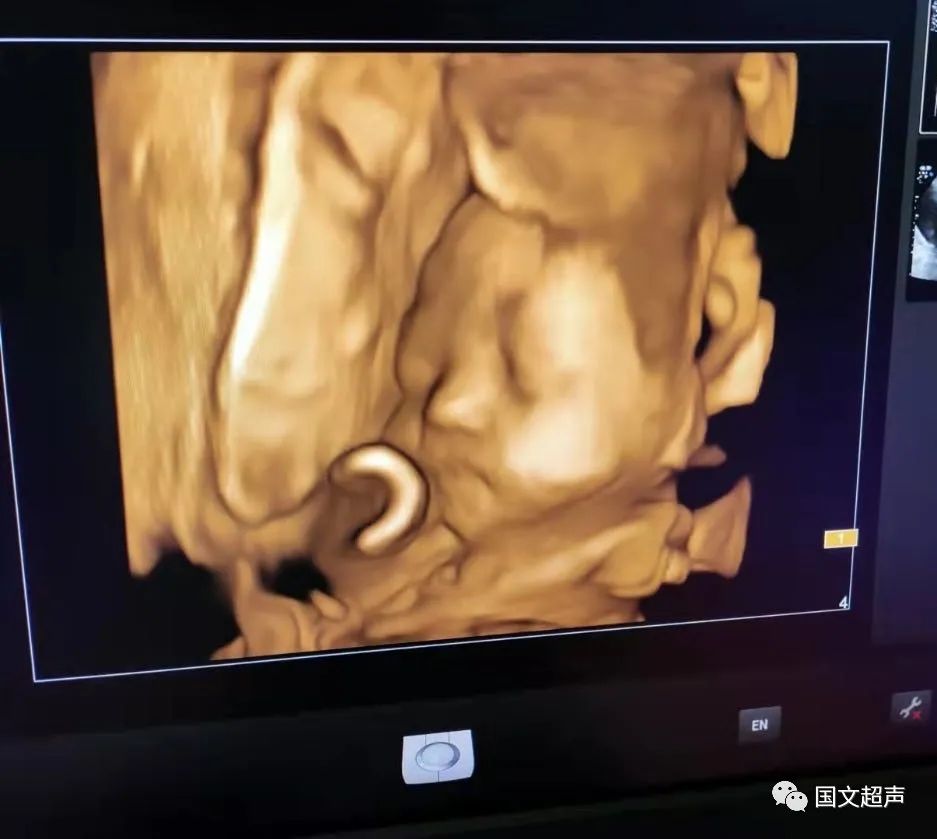

一.飛利浦EPIQ7高端四維彩超

我院目前使用的是飛利浦EPIQ7高端四維彩超,它擁有高品質(zhì)自動(dòng)成像分析技術(shù),分辨率及清晰度高,可以較清晰的顯示宮內(nèi)胎兒的生長(zhǎng)發(fā)育情況,為診斷胎兒先天性畸形,如唇裂、脊柱裂、顱腦發(fā)育異常、骨骼發(fā)育異常、心血管畸形等提供準(zhǔn)確的科學(xué)依據(jù)。